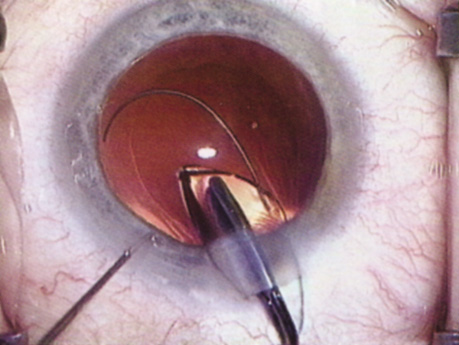

HYDRODISSECTION

Hydrodissection can be performed after the surgeon has successfully completed capsulorrhexis.97 If the capsulorrhexis is not intact, fluid forced around the interior of the capsule may cause the bag to splay open. With capsulorrhexis, hydrodissection is a safe and extremely useful maneuver. Hydrodissection can be thought of as two maneuvers: hydrodelineation and cortical cleaving hydrodissection. By placing a 27-gauge cannula on a syringe filled with balanced saline solution (BSS), the surgeon can direct fluid beneath the residual anterior capsular rim to create a cleavage plane. Depending on the direction the fluid wave takes, different lamellae of the cataract will be separated. Hydrodelineation is the term used when the cleavage plane separates the adult nucleus from the fetal nucleus or the adult nucleus from the more peripheral epinucleus. Hydrodelineation often results in the characteristic golden ring sign (Fig. 11). Cortical cleavage occurs when the cortex is separated from the capsular bag (Fig. 12). Finding the cortical cleavage plane may be facilitated by gently lifting the capsular margin away from the cortex with the BSS cannula before injecting. Several small bursts of fluid allow the surgeon to monitor progress of the fluid wave. When dealing with a soft nucleus, the authors strive to perform true cortical cleaving hydrodissection. For a hard nucleus, hydrodelineation allows manipulation of less of the nuclear bulk, although the remaining epinuclear shell must be addressed in an additional step. Hydrodelineation is particularly useful if the nucleus is not freely mobile after cortical cleaving hydrodissection.

Fig. 11. A crisp “golden ring” is seen from the fluid cleft between the epinucleus and nucleus with hydrodelineation.